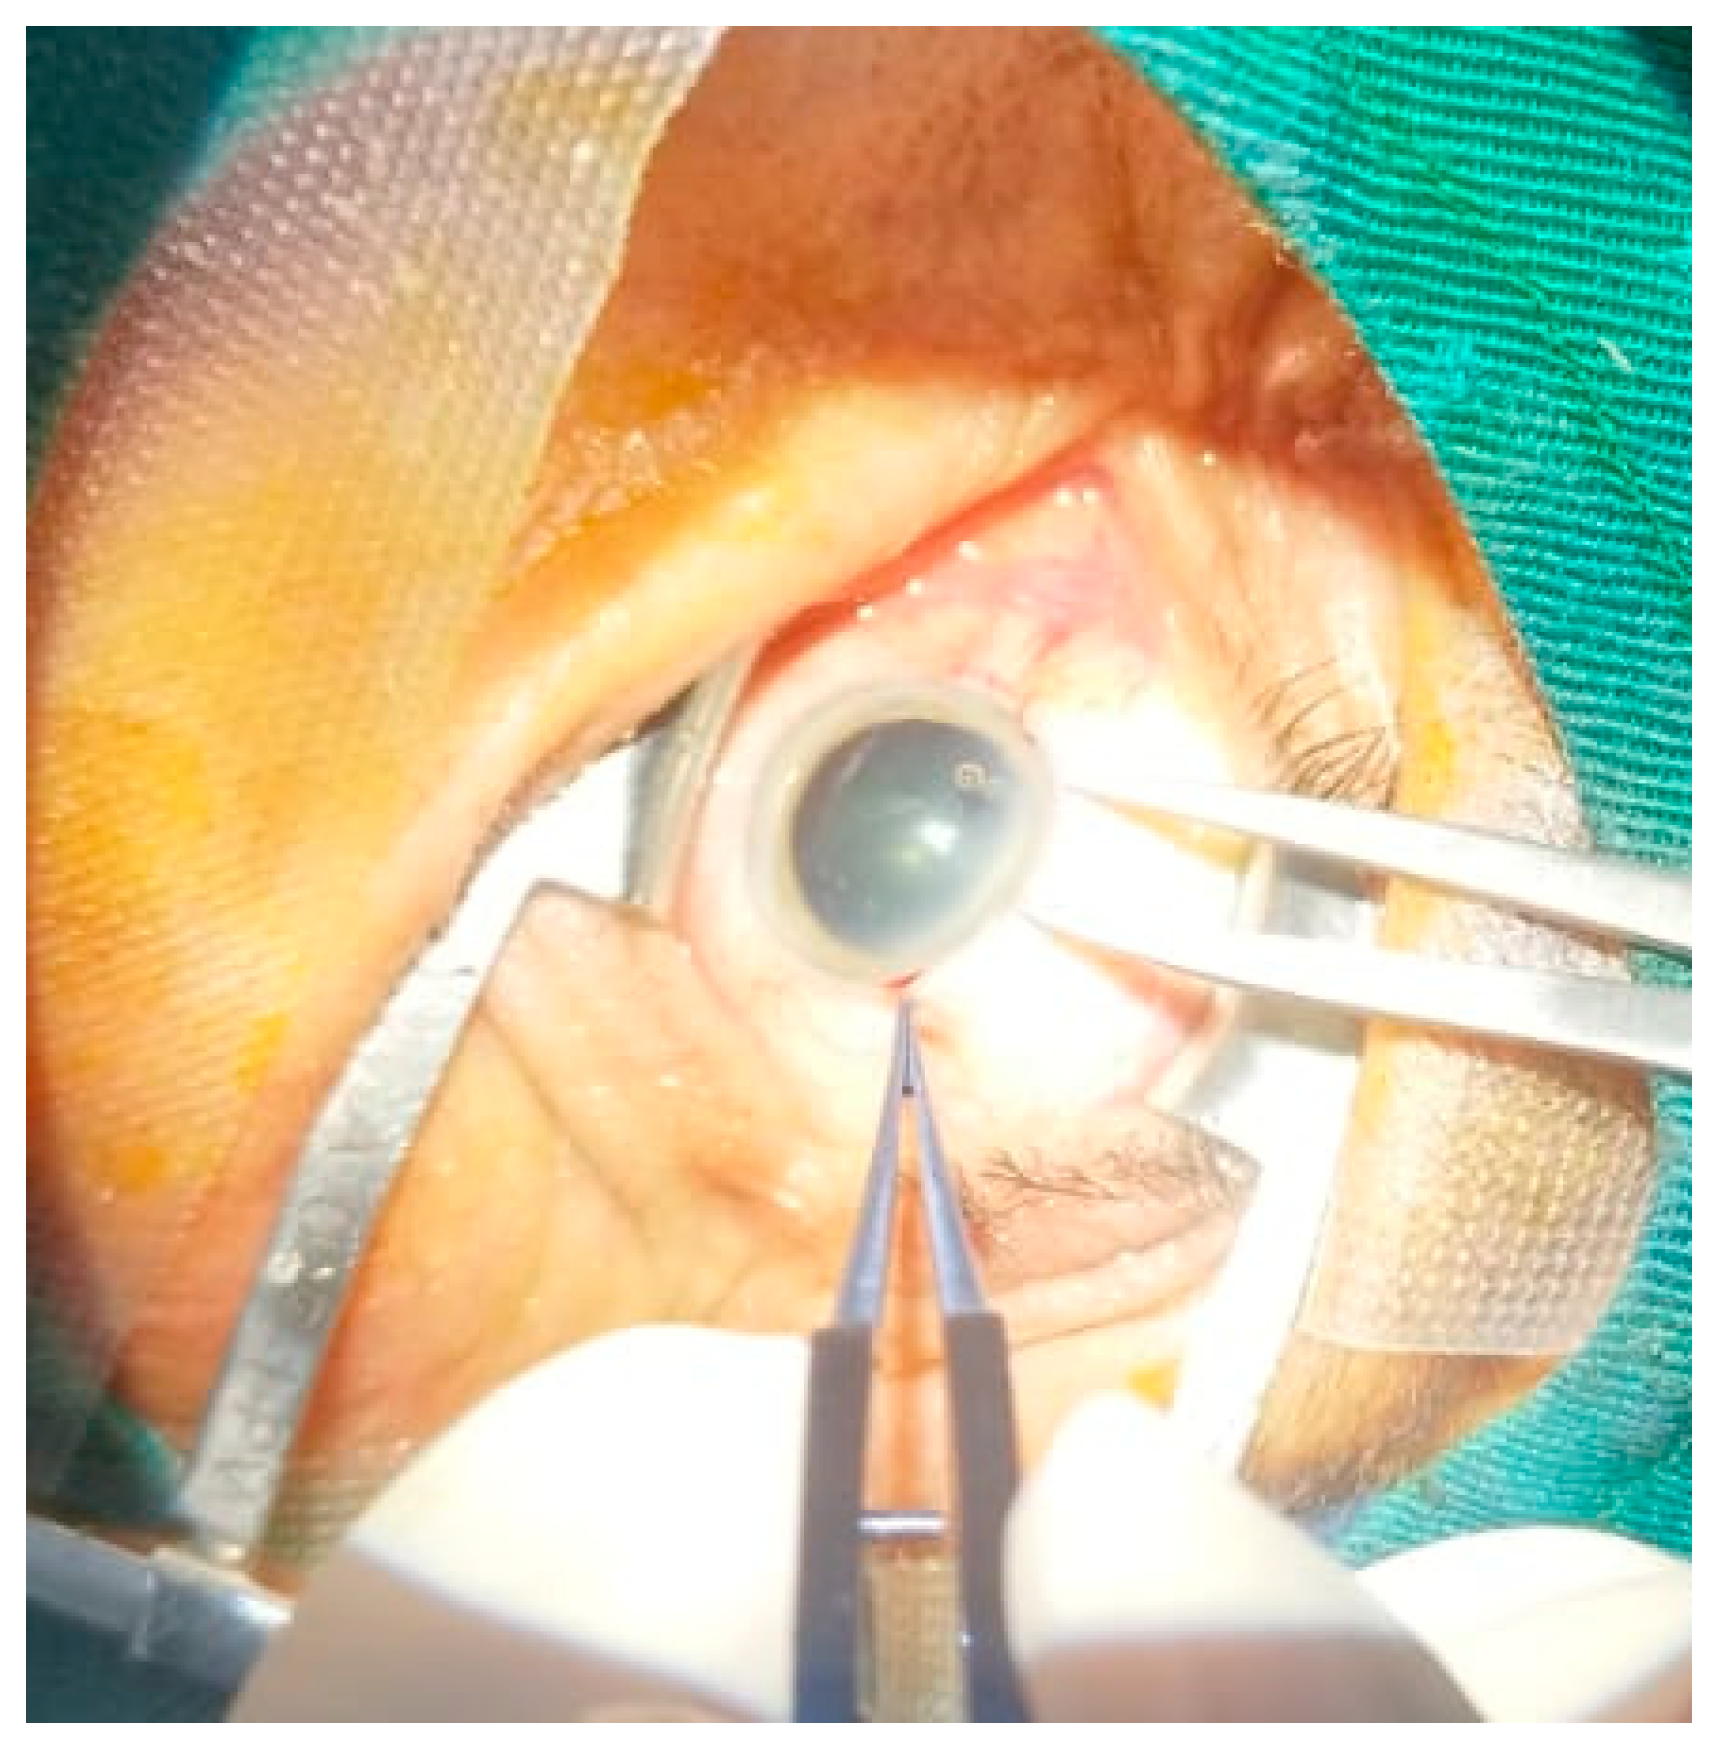

This study is particularly needed as there is limited research on the specific impact of SICS in the Ecuadorian context, where access to ophthalmological care is often restricted. While SICS has been widely studied in other low- and middle-income countries, there remains a gap in understanding its effectiveness in Ecuador, where unique challenges such as an aging population, chronic UV exposure, and systemic comorbidities like diabetes and hypertension are prevalent. This research aims to fill this gap by assessing the outcomes of SICS in improving postoperative visual acuity among patients from coastal Ecuador. Additionally, it will provide valuable insights that can help optimize cataract surgery practices in Ecuador, inform public health strategies, and contribute to reducing preventable blindness in underserved regions. By focusing on this population, the study highlights the potential of SICS as a sustainable and cost-effective intervention tailored to Ecuador’s specific healthcare needs. The novelty of this study is emphasized as the first multicenter analysis of cataract surgery in the Ecuadorian coastal region. This work provides valuable regional evidence to inform visual health policies in low-resource settings (Figure 1).

Figure 1. Small Incision Cataract Surgery (SICS) technique at the Institute of Vision: ongoing surgical procedure.